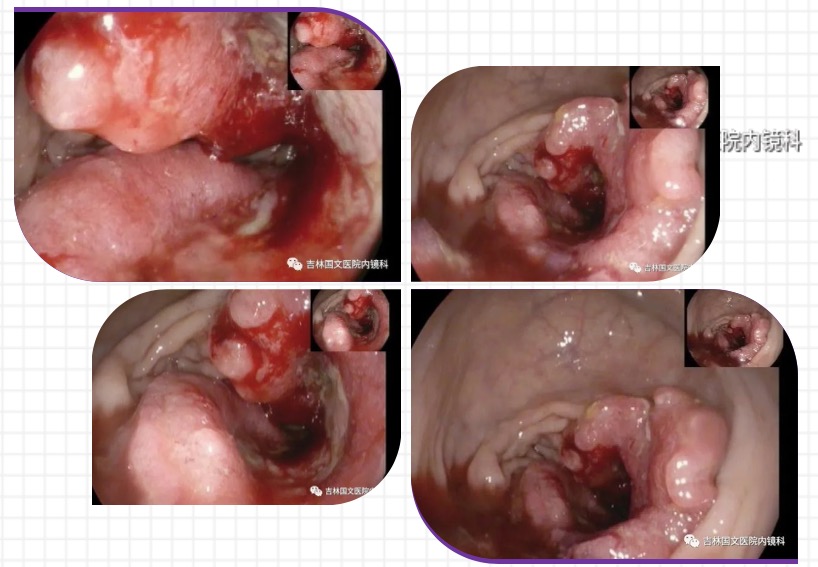

最近就有這樣一起案例,便血后自我診斷為痔瘡,當(dāng)做痔瘡治療了一年多,從未到醫(yī)院詳細(xì)檢查過,近日便血加重,腸鏡檢查后,明確診斷為腸癌,被自己的無知和自以為是給害了。

借此案例,呼吁大家有癥狀一定要到正規(guī)醫(yī)院規(guī)范治療,以免延誤病情,悔恨終生!將傷害降至最低,將癌癥的種子扼殺在搖籃里。

以為是痔瘡 其實(shí)是腸癌